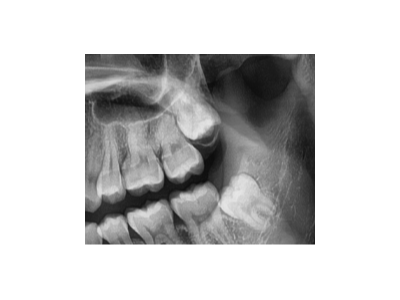

隨著科技發(fā)展,口腔健康越來越被人重視。但是很多人沒有正確的刷牙,長年累月后出現(xiàn)牙周疾病,導(dǎo)致牙齒的脫落。這時候很多老年人會選擇去醫(yī)院,醫(yī)生在經(jīng)過檢查后,給出兩個建議:裝假牙或者進(jìn)行種植牙。對于老年人來…

做種植牙全程需要多長時間呢?

關(guān)于牙齒缺失修復(fù),那么是不是現(xiàn)在大部分的人都會選擇及時修復(fù),而不是讓自己的牙齒長久的出現(xiàn)缺失的問題。不過現(xiàn)在缺牙修復(fù)的方式方法多種多樣,大家會選擇哪一種呢?很多朋友可能會反饋想要做種植牙,那么做種植牙…